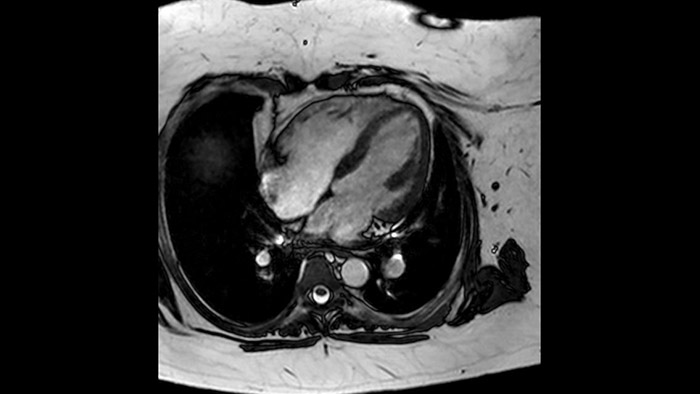

A utilidade diagnóstica e prognóstica da RM cardíaca está aumentando. Avalie a anatomia e a função do coração, usando aquisições cine; obtenha informaçõe sobre perfusão e viabilidade do tecido cardíaco; visualize edema potencial com sequência de sangue preto; acesse e até quantifique a caracterização tecidual com CardiacQuant.